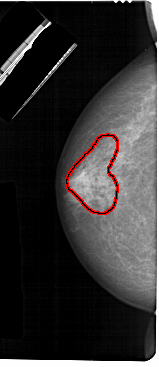

A_1302_1.LEFT_MLO

FILE: A_1302_1.LEFT_MLO.OVERLAY

TOTAL_ABNORMALITIES 1

ABNORMALITY 1

LESION_TYPE CALCIFICATION TYPE PUNCTATE-AMORPHOUS DISTRIBUTION REGIONAL

ASSESSMENT 4

SUBTLETY 3

PATHOLOGY BENIGN

TOTAL_OUTLINES 1

BOUNDARY